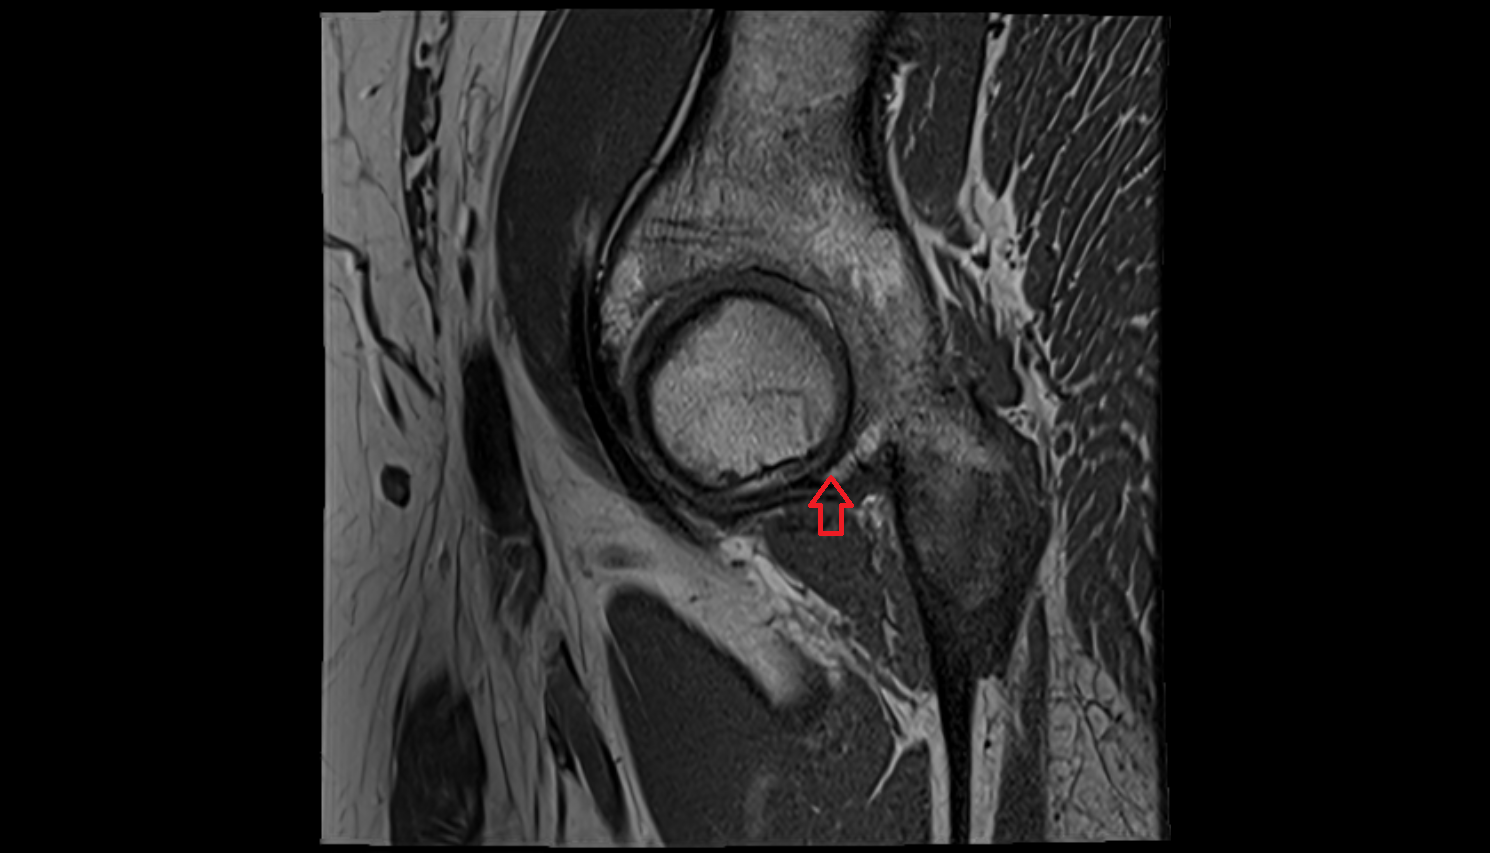

- Medial meniscus

- Lateral meniscus

- Posterior horn of medial meniscus

- Posterior horn of lateral meniscus

- Anterior cruciate ligament

- Posterior cruciate ligament